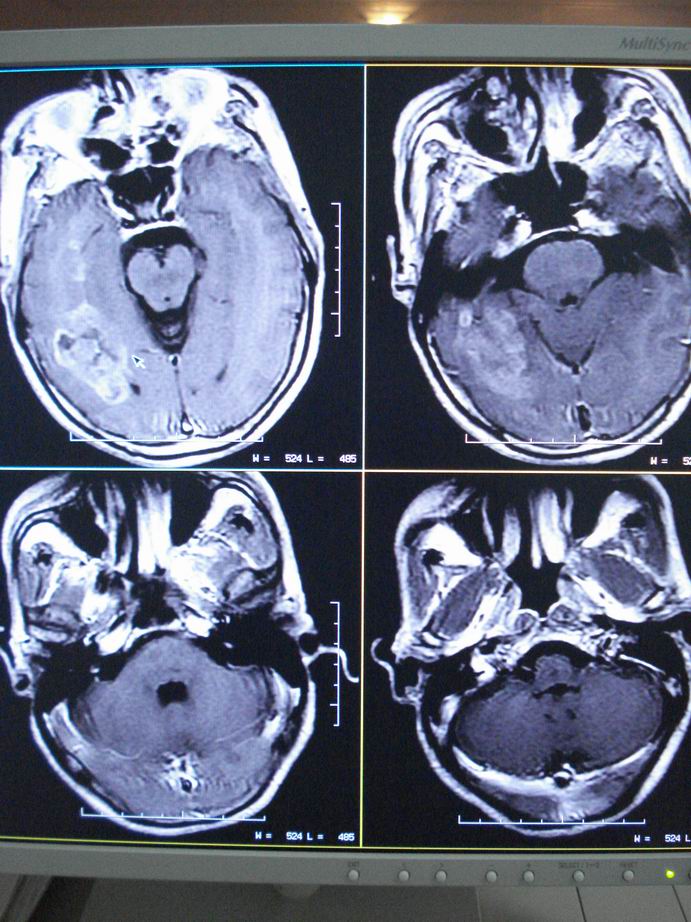

男60岁,左侧肢体乏力及精神异常10天,血压正常,血常规,肝肾功正常,腰穿无异常,请教颅内多发病灶,考虑什么?感染?肿瘤(转移性?)还是其它?

考虑为颅内多发转移瘤

脑内多发性转移瘤。

淋巴瘤较转移瘤可能大。

脑内多发占位性病变,首先考虑感染性病变,其次是转移瘤。

结合病人高龄,考虑转移瘤